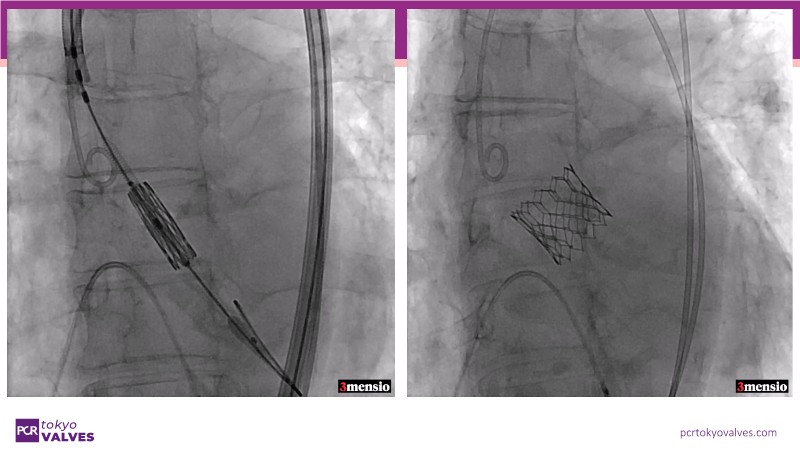

Explore the latest strategies for optimizing outcomes in Asian and international patients with small body size. Through case presentations, surgical experiences, and the latest data on device performance, gain valuable insights into treating aortic stenosis more effectively. Discover how these advancements can enhance patient care and improve procedural success.